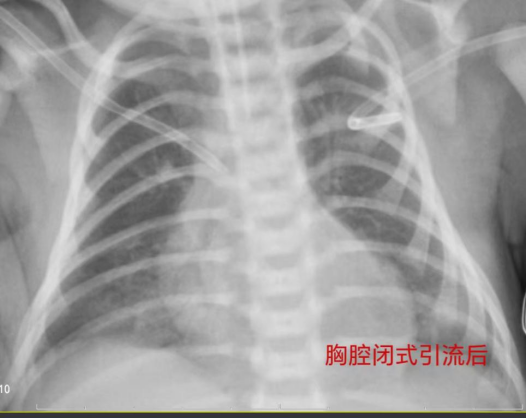

中午12点多,患儿转入新生儿科,许德权副主任带领医护团队,为患儿紧急完善相关检查,确诊为新生儿急性呼吸窘迫综合征并发双侧张力性气胸,遂立即为患儿实施双侧胸腔闭式引流联合高频呼吸机辅助通气。操作顺利完成后,宝宝呼吸困难明显好转,在场的医护人员暂时松了一口气,但他们丝毫不敢懈怠,守护在宝宝身边,时刻关注病情变化。